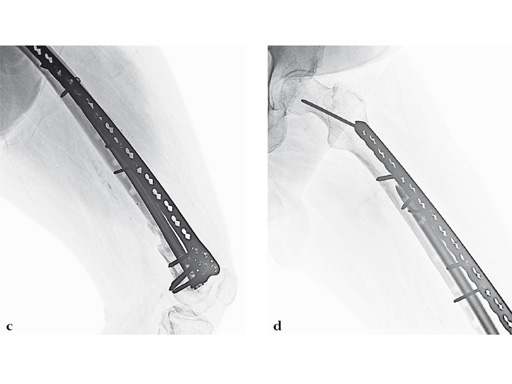

Case 2: A 69-year-old man following revision total knee arthroplasty with a megaprosthesis, requiring an osteotomy of his femoral shaft for realignment of his femoral component. The patient developed a nonunion of his osteotomy and subsequently fractured the stem of his megaprosthesis.

Surgical treatment of this nonunion consisted of compression plating using the VA-LCP Curved Condylar Plate. The arthroplasty components were stable. The proximal piece of the stem was extremely well fixed. Variable-angle locked screws were targeted between his femoral shell and stem in the distal segment allowing excellent distal fixation such that an articulated tensioning device could be attached proximally and the nonunion could be compressed and the alignment improved.

Case 3: A 53-year-old man with hypotestosteronism, low vitamin D levels, and calcium metabolism problems. Recalcitrant atrophic nonunion of his distal femur after three surgical attempts with an extension and flexion contracture of his knee.

The VA-LCP Curved Condylar Plate was used to avoid previous enlarged screw holes and allow for stable fixation in the patient's osteoporotic distal segment. Secondary to his metabolic and mechanical problems, the decision was made to proceed with an endosteal implant and place interlocking screws through that implant from the VA-LCP Curved Condylar Plate. The combination of the retrograde/antegrade femoral nail and VA-LCP provides a very stable mechanical environment for the expected prolonged healing response.